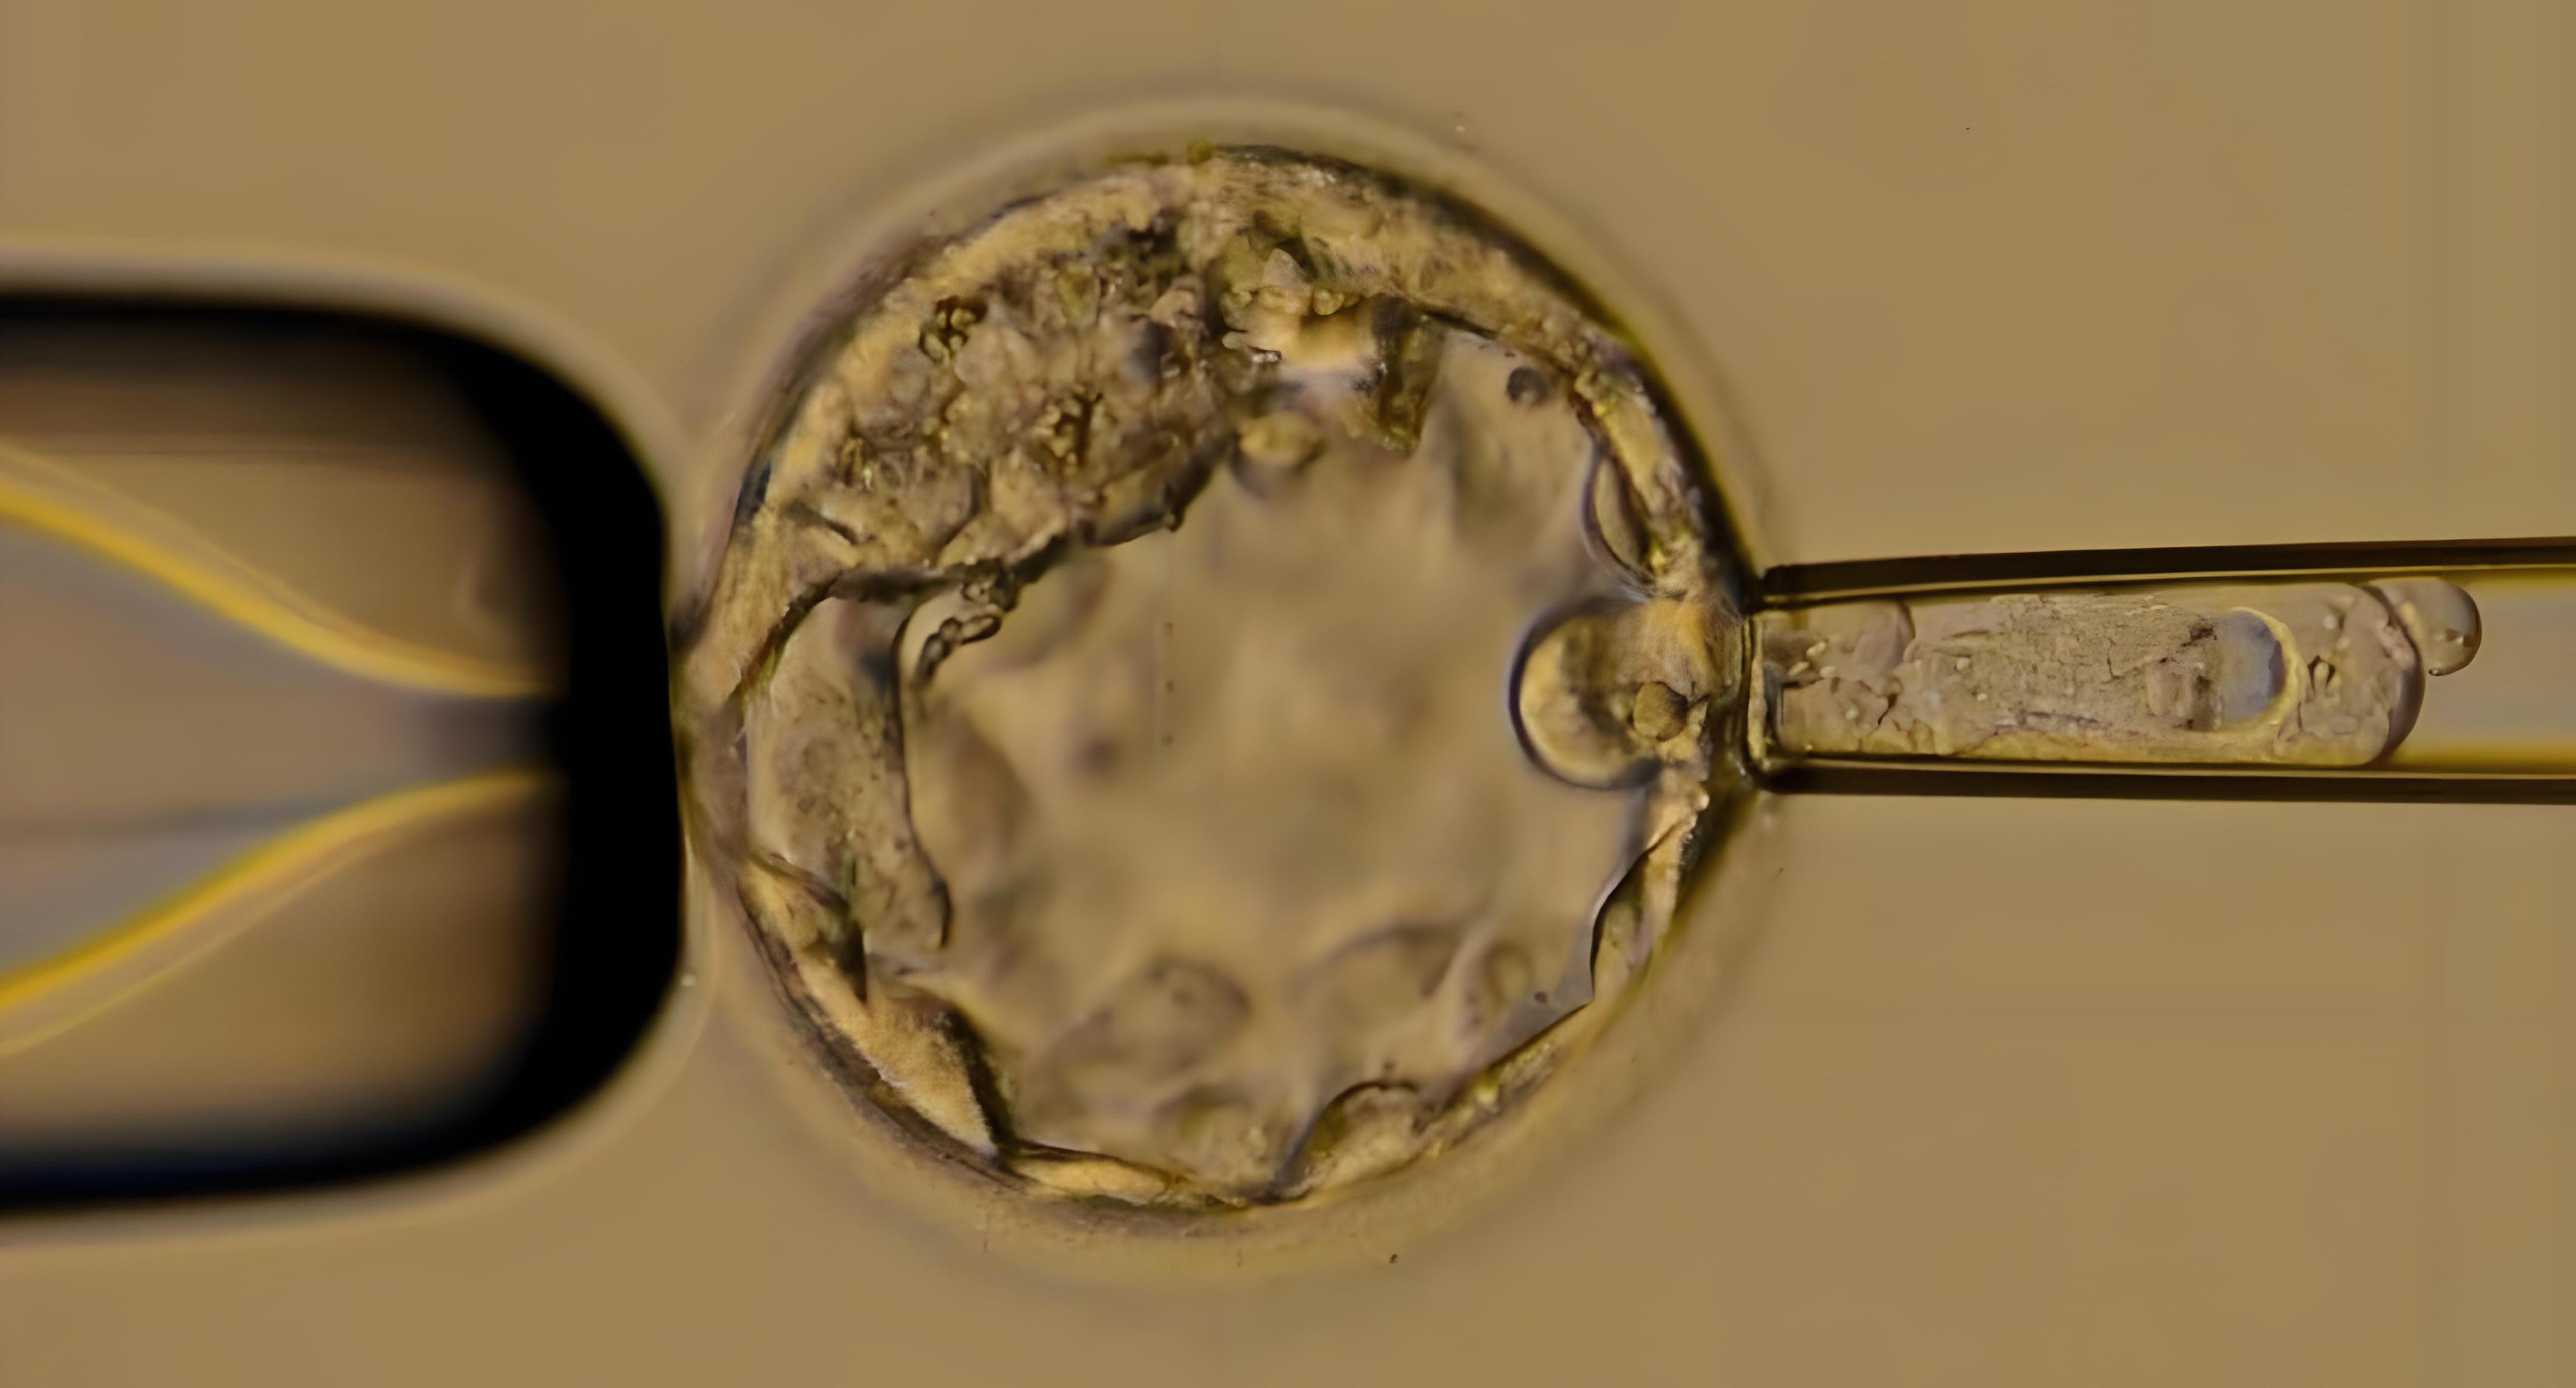

注:女方取卵时,男方需进行取精(常规法或专家运用睾丸穿刺技术获取)。之后,美国试管婴儿专家将运用ICSI单精子注射技术,将优质健康的精子直接注射到卵胞浆内,使精卵细胞快速结合形成受精卵。